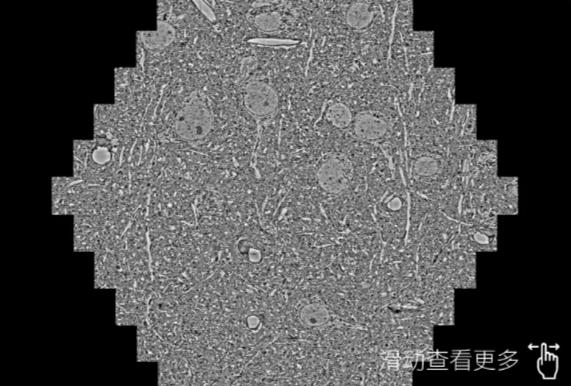

鼠脑切片。左图使用乐东蔡司乐东扫描电镜MultiSEM706对165μmx143pm面积区域成像,耗时仅需1.5秒。右图为鼠脑切片中30μm区域放大效果。样品由芝加哥大学B.Kasthuri提供。

使用蔡司高速乐东扫描电镜MultiSEM对1mm²人脑皮层组织进行高分辨成像,并对其中的各种细胞结构进行三维重构分析。左图展示了2x3mm²组织平面中锥体神经元的三维重构效果。右图显示了局部体积神经元三维重构。图像由哈佛大学chtman实验室提供,渲染图由D. Berger 制作。